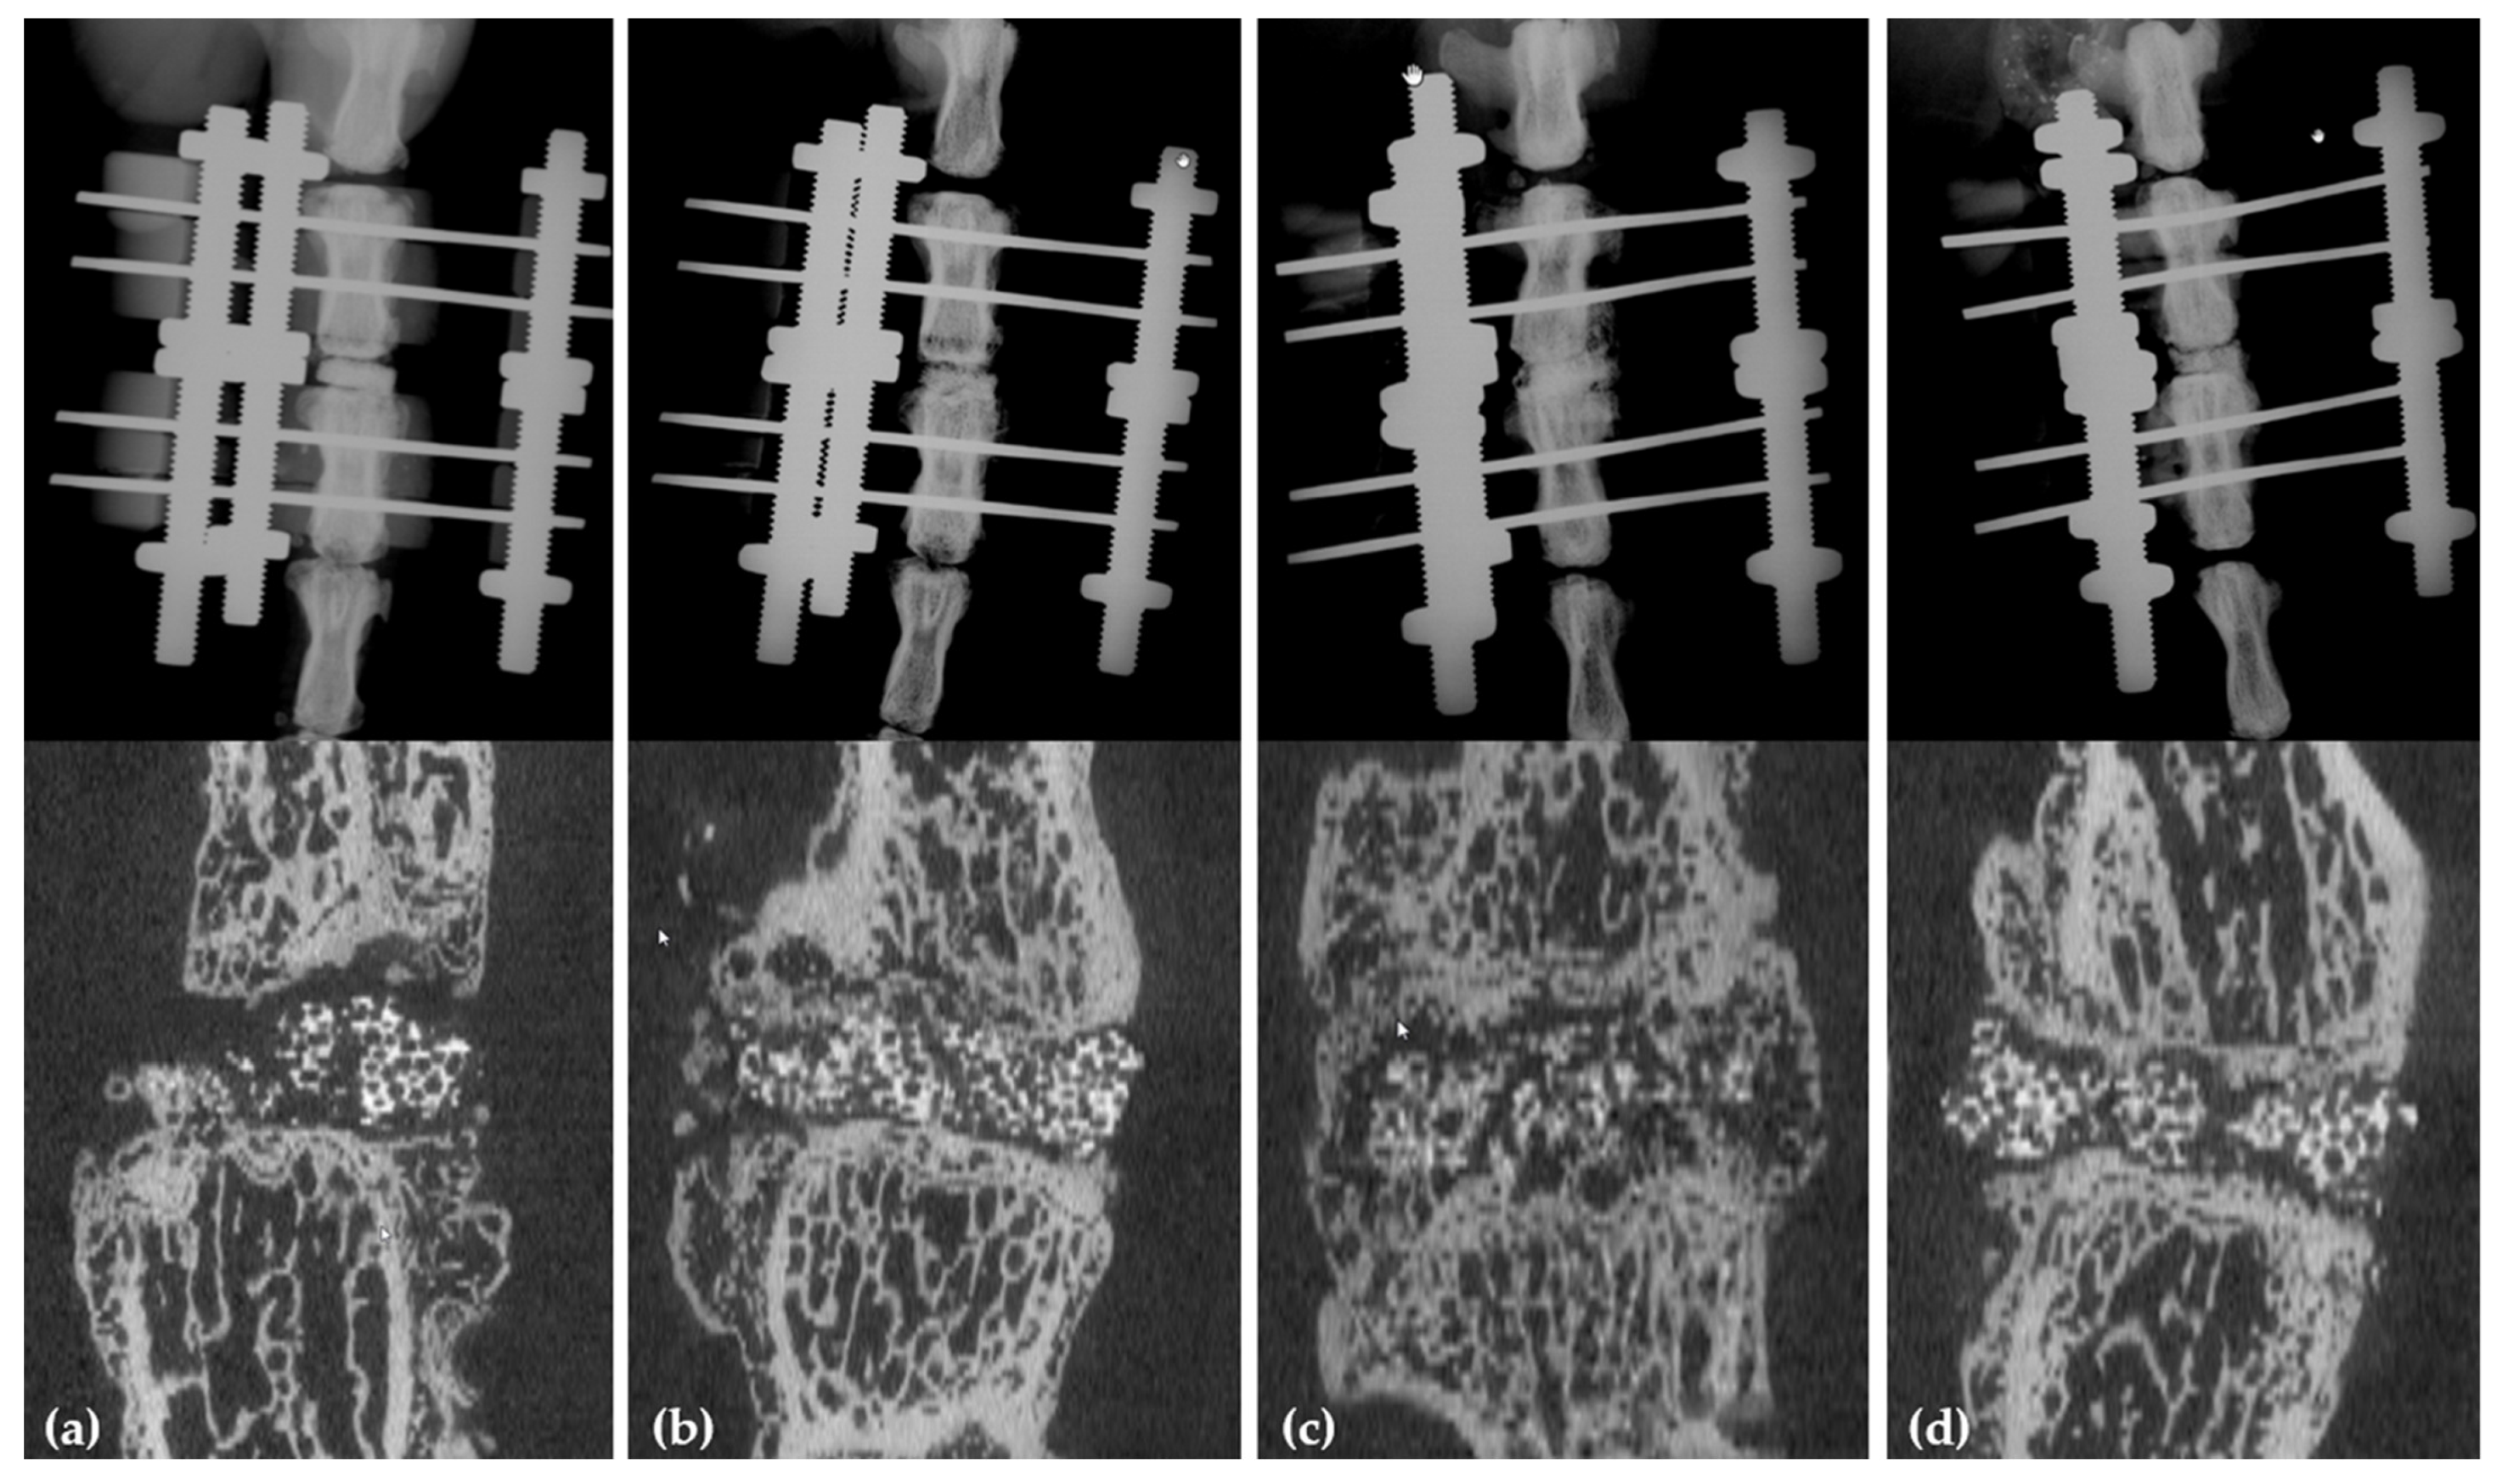

4.2. Data Analysis and Interpretation

4.2.1. X-rays and µCT